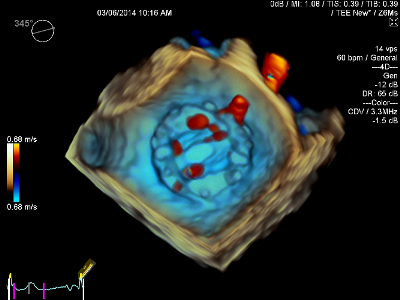

True Volume TEE Imaging

僧帽弁・大動脈弁を含む広範囲の3D画像や血流情報を加えた3Dカラードプラを心電図同期なく,リアルタイムに描出します。画像取得時の呼吸コントロールが必要なく,術後の弁周囲逆流の評価なども瞬時におこなえ,より安全で確実な施術に貢献します。